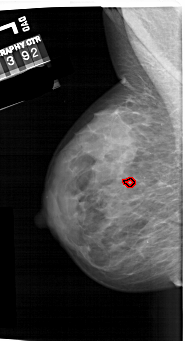

A_1257_1.RIGHT_MLO

LEFT_MLO LINES 6466 PIXELS_PER_LINE 3511 BITS_PER_PIXEL 12 RESOLUTION 43.5 OVERLAY

FILE: A_1257_1.LEFT_MLO.OVERLAY

TOTAL_ABNORMALITIES 1

ABNORMALITY 1

LESION_TYPE CALCIFICATION TYPE PLEOMORPHIC DISTRIBUTION CLUSTERED

ASSESSMENT 4

SUBTLETY 1

PATHOLOGY MALIGNANT

TOTAL_OUTLINES 1

BOUNDARY